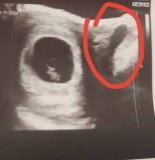

Hi. 9mar buat test, double line. 13mar scan baby dah 8weeks,1day. Sepanjang bulan puasa ni loya teruk tapi tak muntah. Takde selera makan so start sakit ulu hati. Doc bagi ubat gastrik. Berat dari 81kg turun 76kg with a month. Mcm mana ye nak atasi masalahnya loya/mual ni 😭😭#bantujawab #Needadvice